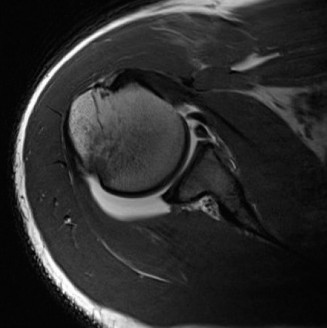

CASE 11 A 33-year-old male presents to the ED after a fall during a soccer game. He reports significant right shoulder pain and limited ROM. An x-ray taken in the ED is shown below (Fig. 2–29).

Figure 2–29

The correct answer is (A). The ED image shown in Figure 2–29 includes only an AP view of the right shoulder. In the setting of an acute injury and pain, technicians may be hesitant to obtain additional views. A single view, however, is insufficient to diagnose either a fracture, as orthogonal views are required, or a shoulder dislocation which is best seen on an axillary view (see Fig. 2–30). Answers B and C are inappropriate as a diagnosis has not been established yet and a dislocation or fracture must be conclusively ruled out. Answers D and E may be options that are exercised in the clinic but do not represent the next step in the management of this patient.